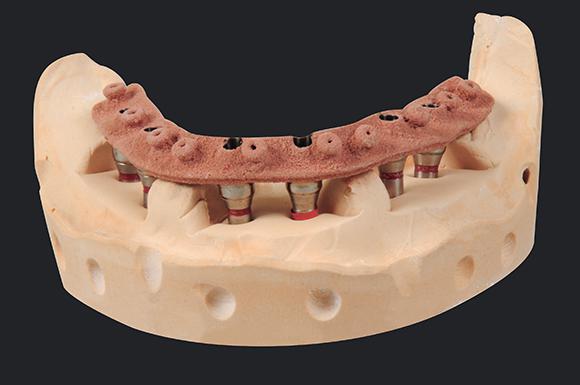

At CRH Oral Design , all of our implant-retained overdenture and fixed denture are designed by our technicians using 3-D CAD technology and milled with CAM technology using Straumann, Atlantis and Panthera Dental .

An implant supported prosthesis derives its entire support from dental implants. This type of restoration may be fixed (screw retained) or removable (attachment retained). Only a clinician can remove a screw retained implant supported overdenture, compared to an implant-supported attachment retained (fixed-detachable prosthesis) that can be removed by the patient or clinician. Fixed-detachable implant prosthetics sometimes need to have a mesiostructure such as cast metal framework over the bar to reinforce acrylic resin.